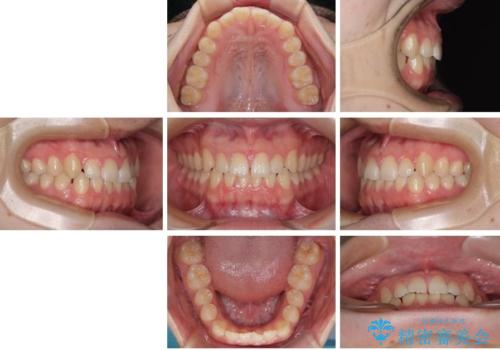

- 「前歯のすきっ歯が気になる」「食べ物が歯の間に詰まりやすい」とのお悩みで来院された20代男性の患者様です。

歯と歯の間に隙間がある**空隙歯列(すきっ歯)**は、見た目の問題だけでなく、食片圧入による歯肉の腫れや、隣接面う蝕のリスク増加につながることがあります。

診査により舌突出癖が認められました。この癖は、すきっ歯の原因となるだけでなく、矯正後の後戻りリスクを高めます。